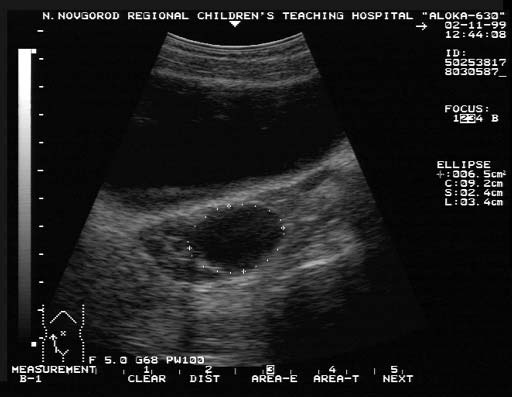

Фолликулярная киста на УЗИ-исследовании

Наиболее многочисленной группой яичников, имеющей основное практичное значение, являются фолликулярные кисты. Эти кисты представляют собой новообразование доброкачественного характера, заполненное невоспалительной жидкостью.